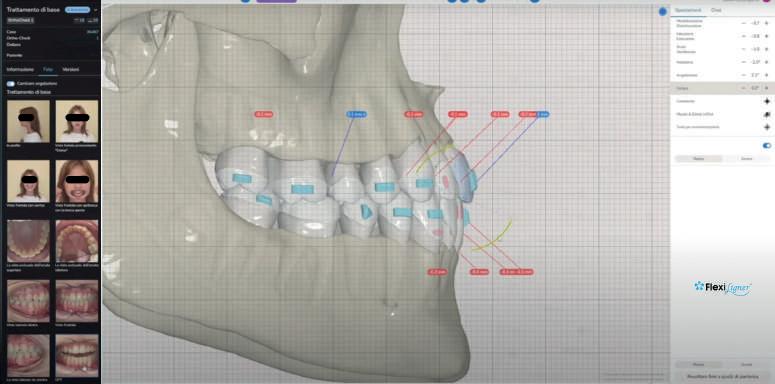

FlexiLigner, nella produzione dei suoi allineatori ortodontici, mette a disposizione il suo software FlexiSoft, una piattaforma online innovativa che integra avanzati strumenti ortodontici per il controllo e la pianificazione dei trattamenti. Include Ortho Check, Ortho Tuner e Photo Editor che offrono visualizzazioni, azioni 3D interattive, movimentazioni dentali precise, analisi dell'occlusione e gestione dei movimenti mandibolari; il tutto gestendo simmetrie facciali e dentali mediante le foto del viso e intraorali. Attraverso la funzione opzionale Cone Beam + Modello 3D, è possibile inoltre controllare dettagliatamente lo spessore osseo, prevenendo complicazioni come le recessioni gengivali e avere il controllo completo delle movimentazioni reali delle radici anatomiche. Inoltre, un'app mobile facilita la comunicazione con il laboratorio,

La progettazione computerizzata del trattamento ortodontico offre la possibilità al professionista di condividere con la persona assistita la visualizzazione dei percorsi terapeutici stimolando una migliore aderence alla gestione della terapia.

L’approccio motivazionale al rispetto delle indicazioni della terapia è fondamentale per il successo della stessa, e le terapie con allineatori ortodontici invisibili, sono preferite dalle persone assistite di tutte le età e con diverse complessità di trattamento, poiché rispettano la discrezione del trattamento e salvaguardano la vita di relazione. L’innovazione tecnologica permette, attraverso sofisticati strumenti di supporto, di condividere attraverso piattaforme on-line o con applicazioni mobili, di interagire con la persona assistita e visualizzare i movimenti

garantendo un'operatività continua e accesso rapido ai dati clinici. www.flexiligner.it e riservato ai medici www.flexiligner.it/medici/